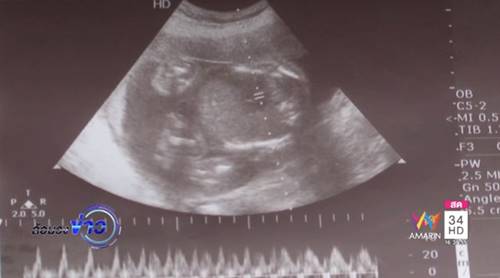

ในส่วนของเอกสารหลักฐานที่ทีมข่าวอมรินทร์ ทีวีนำมาให้คุณหมอร่วมตรวจสอบนั้น คุณหมอบอกว่ายังไม่สามารถยืนยันได้ว่าหญิงคนนี้ท้องลูกแฝดจริง นอกจากจะมีแผ่นฟิล์มที่เห็นภาพเด็กทั้ง 2 คนพร้อมกัน แต่คุณหมอตั้งข้อสังเกตว่า ขนาดของมดลูกคนไข้ที่ขยายยังไม่กว้างพอที่จะมีเด็ก 2 คนในท้อง ที่สำคัญบันทึกการตรวจครรภ์ ระบุว่า กำหนดคลอดวันที่ 7 มิถุนายน 2560 แต่วันคลอดจริงวันที่ 28 พฤษภาคม 2560 สรุปอายุครรภ์ 38 สัปดาห์ ซึ่งตามปกติแล้วหญิงที่ตั้งครรภ์ลูกแฝดจะไม่สามารถอุ้มท้องรอได้นานถึง 38 สัปดาห์ เพียง 36 สัปดาห์ ก็ต้องคลอดแล้ว